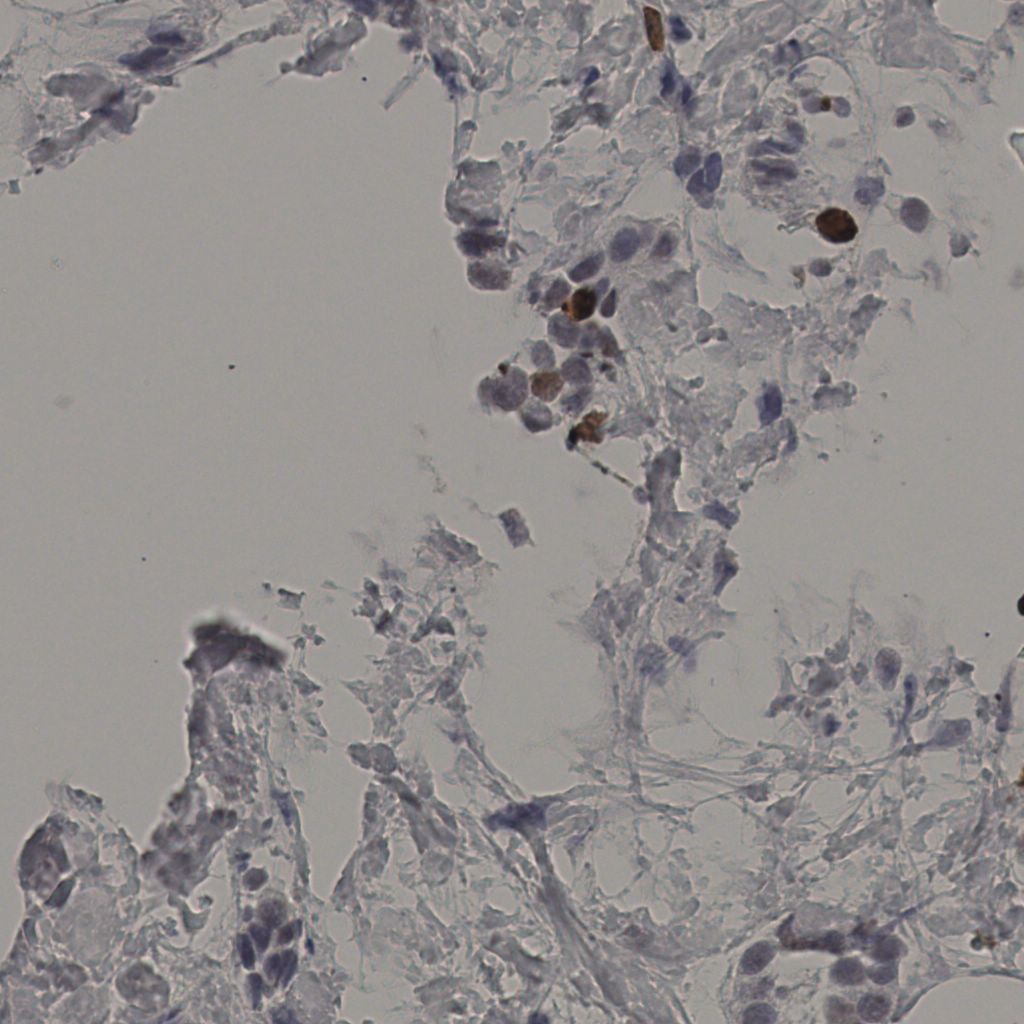

缩略图

标记后

标记前